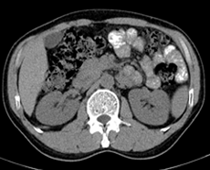

患者,男,57,常年不吃午饭,近一个月来腹部隐痛,无明显黄疸,明天进行增强扫描,图象另上传,麻烦各位帮忙一起看看讨论讨论

肝外胆管扩张,胰头增大,肠系膜上静脉似有包埋征象。

考虑:胰头占位性病变,建议增强进一步检查。

肝内外胆管扩张,胆管未端阻塞,建议mri检查

考虑肝总管或胆总管占位性病变,建议mrcp或ercp.

肝外胆管扩张,胆管未端阻塞?建议mri检查或mrcp或ercp检察院查.

胰头增大,胆总管增宽,考虑胰头癌可能性大,明天看增强片有助诊断.